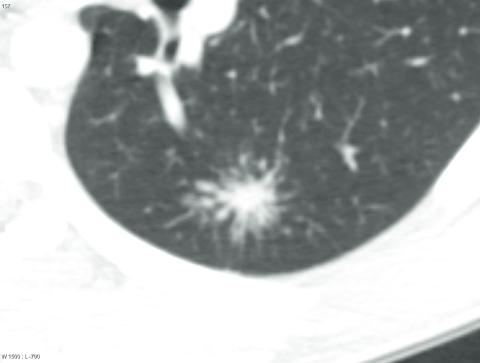

En 25-årig mand havde gennem flere måneder bemærket hævelse af lymfeknuder på halsen, træthed og let hoste. På mistanke om lymfom blev der foretaget eksstirpation af en lymfeknude, og man fandt granulomatøs inflammation med tætliggende epitelcellegranulomer og kæmpeceller. Mange granulomer havde central nekrose. En high resolution-CT af hals og thorax viste flere patologisk forstørrede lymfeknuder cervikalt og mediastinalt samt flere > 1 cm store noduli i lungerne, hvilket var foreneligt med galaxy sign (A). På baggrund af radiologiske og histologiske fund samt en positiv familieanamnese med sarkoidose konkluderede man, at den mest sandsynlige diagnose måtte være sarkoidose. Galaxy sign er et sjældent radiologisk tegn, hvor noduli ligger så tæt, at de morfologisk ligner en stor nodulus omgivet af mange mindre noduli og hermed får lighed med en galakse (B) [1, 2]. Forandringen er ikke patognomonisk for sarkoidose, men kan bruges som diagnostisk ledetråd og interessant supplement til den samlede vurdering af patienten [2, 3]. Galaxy sign kan ses hos patienter med sarkoidose, aktiv tuberkulose, spikulerende lungetumorer eller pneumokonioser [2, 4].